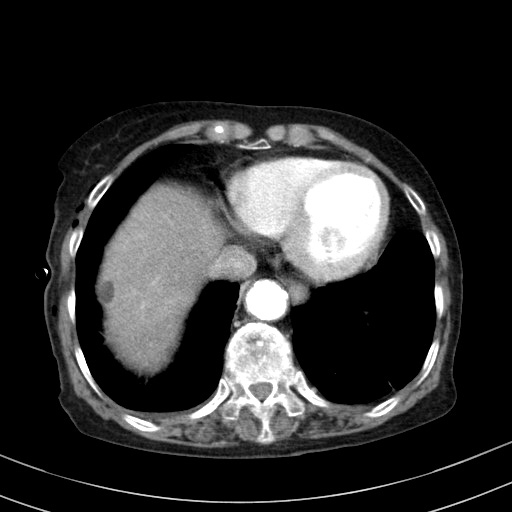

그런데, 이 환자는 초음파영상을 하기 며칠 전에 우상복부의 불편한 느낌과 약간의 압통을 호소하여, 담도결석의 재발 여부를 확인하기 위해 CT를 촬영했던 상태였습니다. 해당 CT 영상에서 간 우엽에 간내석회화와 단순낭종의 존재를 이미 발견해서 알고 있었던 상태였습니다.